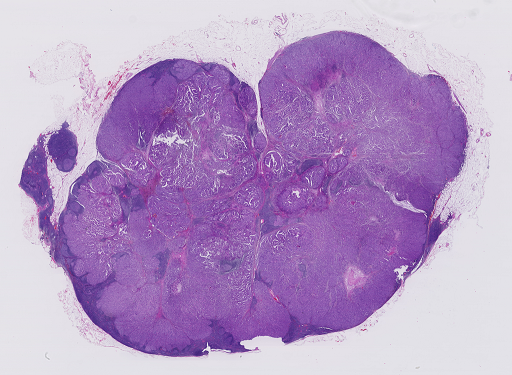

For qualitative ROI detection evaluation check Fig. 3.

Refer to caption

(a)

(b)

Figure 3: Qualitative view of ROIs recognized by Suffy through its Patch Classification. (a) An example WSI from the test set of the CAMELYON16 dataset [3]. (b) ROIs are identified by Snuffy with black lines delineating the ground truth ROIs.